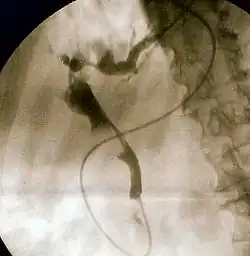

Fluoroscopic image of common bile duct stone seen at the time of ERCP. The stone is impacted in the distal common bile duct. A nasobiliary tube has been inserted.